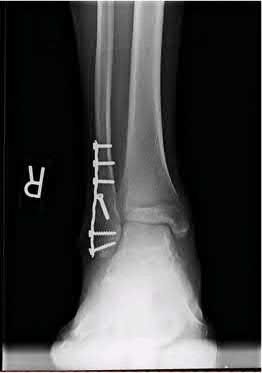

A 64-year-old woman is thrown off a horse, sustaining the injury shown in Figures A and B. She undergoes surgical fixation as seen in Figures C through E. What is the most commonly reported complication of this procedure?

The patient in the scenario has a 2-part proximal humerus fracture treated with a locking plate as seen in Figures A-E. The most common complication with the use of this implant is screw penetration. The terms screw cut out and penetration are often used interchangeably in the literature with cut out appearing more frequently in reports regarding intertrochanteric fractures.

Owsley et al retrospectively reviewed 53 proximal humerus fractures treated with locking plates and the same post-operative protocol. The most common complication was screw cut out or penetration, followed by varus displacement. They concluded that 3 and 4-part fractures in patients over 60 years have a higher incidence of failure.